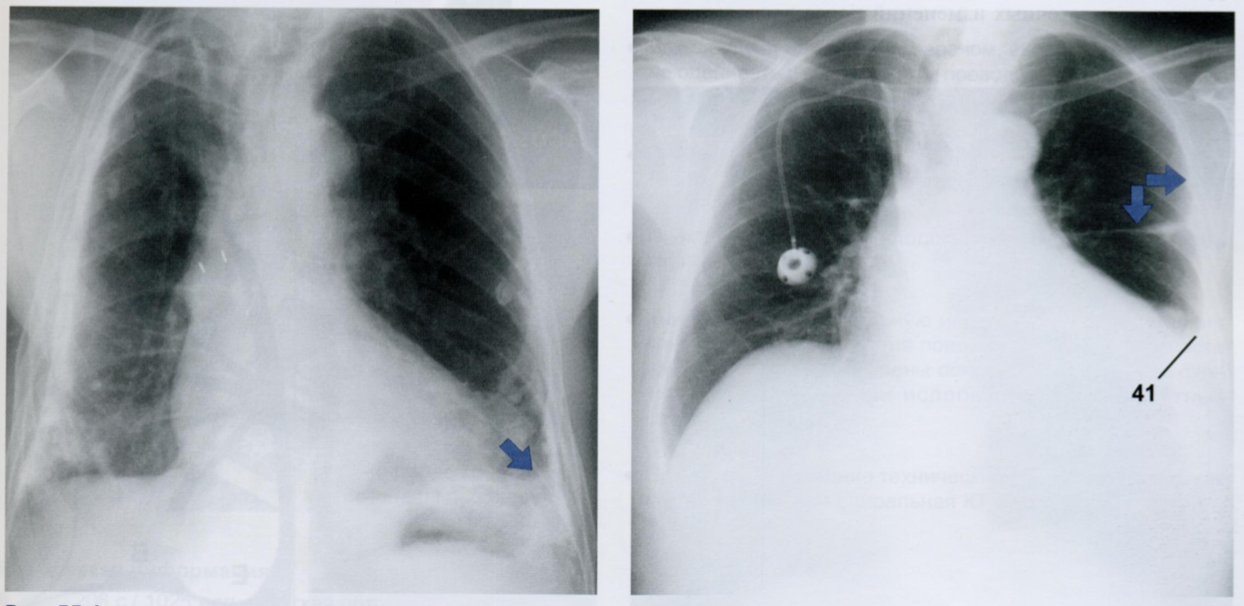

11

Оцените снимки.

Что из себя представляет фиброз плевры?

Физброз представляет собой грануляционную ткань, которая может вторично обызвествляться.

На снимке приведен пример плеврального фиброза в базальном отделе слева (стрелка). Изменения плевры в базальном отделе могут симулировать выпот с небольшим количеством жидкости из-за того, что реберно-диафрагмальный синус выглядит размытым.

Междолевой фиброз (стрелки) с обеих сторон граничит с воздушной тканью легкого и по этому отчётливо определяется в виде линейной тени (второй снимок).

На этой ренттенограмме также имеется утолщение плевры (горизонтальная стрелка) слева в латеральных отделах и сопутствующий выпот в плевральной полости (41).